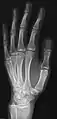

- Hand - DP and Oblique

Left hand by dorsoplantar projection

Lateral projection

Oblique projection